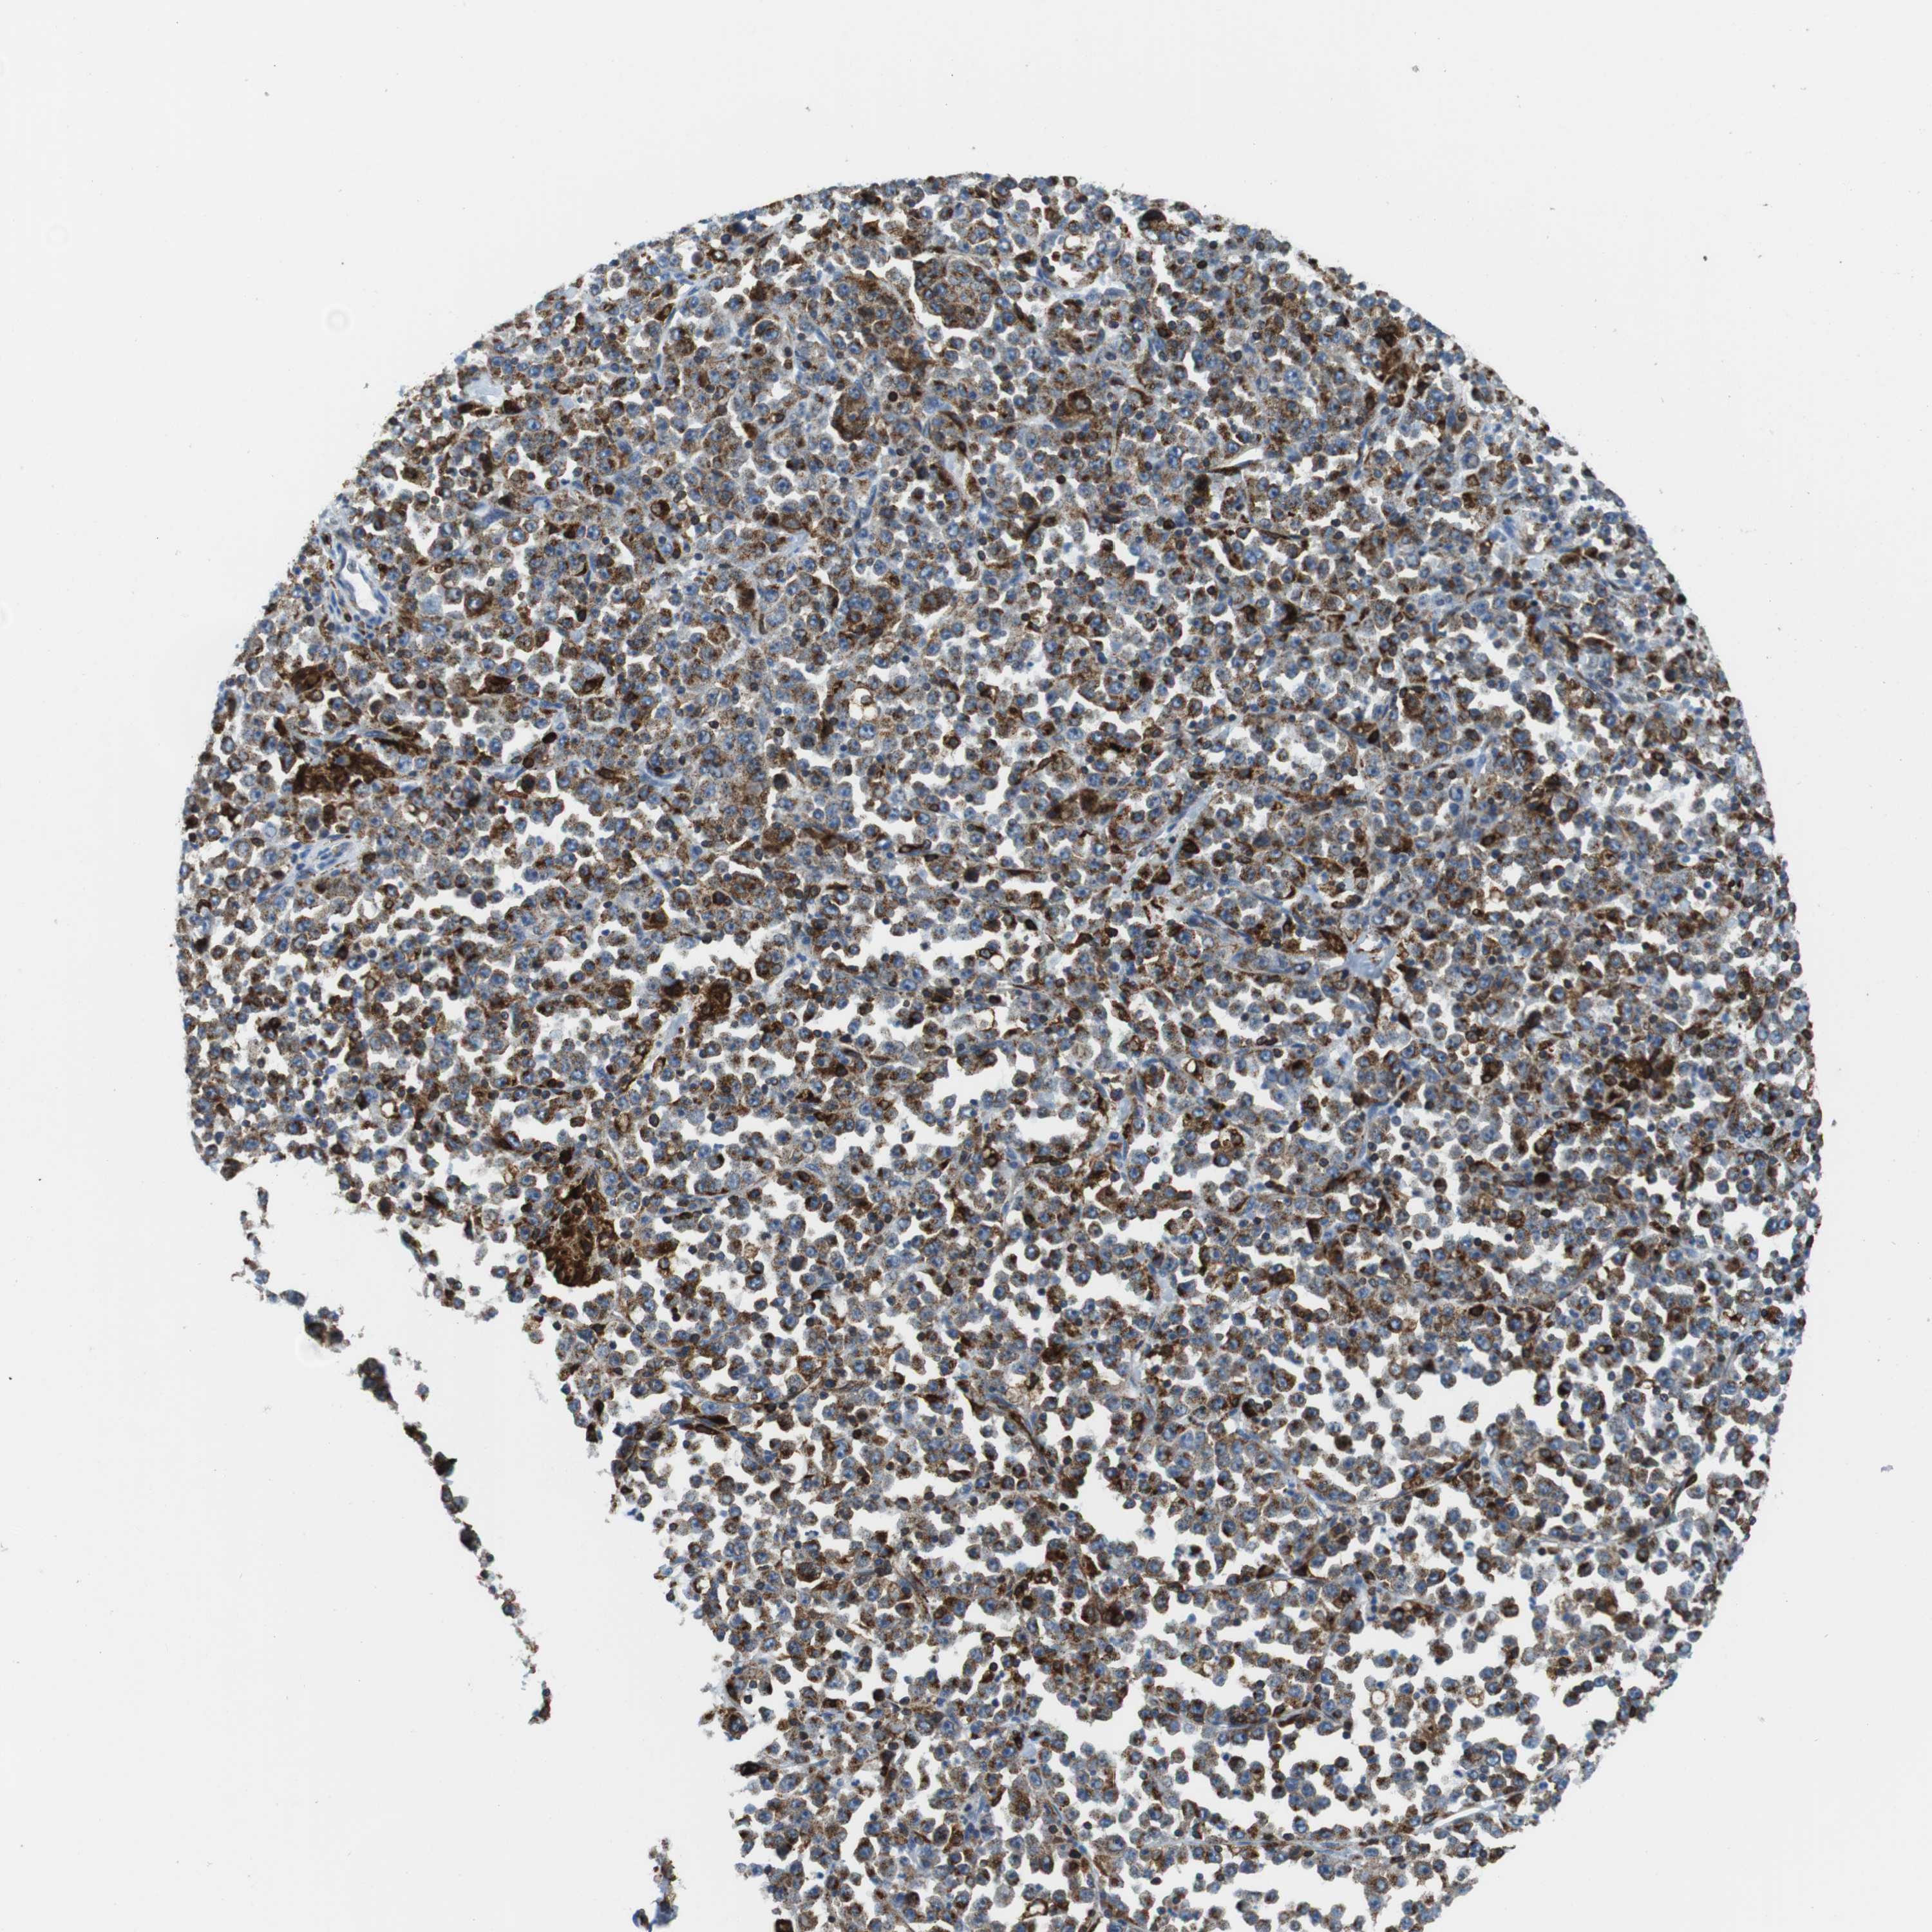

STOMACH CANCER - Protein expressioni

A mouse-over function shows sample information and annotation data. Click on an image to view it in a full screen mode. Samples can be filtered based on level of antibody staining by selecting one or several of the following categories: high, medium, low and not detected. The assay and annotation is described here.

Note that samples used for immunohistochemistry by the Human Protein Atlas do not correspond to samples in the TCGA dataset.

Antibody stainingi

Antibody staining in the annotated cell types in the current human tissue is reported as not detected, low, medium, or high, based on conventional immunohistochemistry profiling in selected tissues. This score is based on the combination of the staining intensity and fraction of stained cells.

Each image is clickable and will lead to virtual microscopy that enables deeper exploration of all samples and also displays staining intensity scores, fraction scores and subcellular localization as well as patient and tissue information for each sample.

Antibody CAB016084

Staining

High

Medium

Low

Not detected

Intensity

Strong

Moderate

Weak

Negative

Quantity

>75%

75%-25%

<25%

None

Location

Nuclear

Cytoplasmic/membranous

Cytoplasmic/membranous,nuclear

Adenocarcinoma, NOS